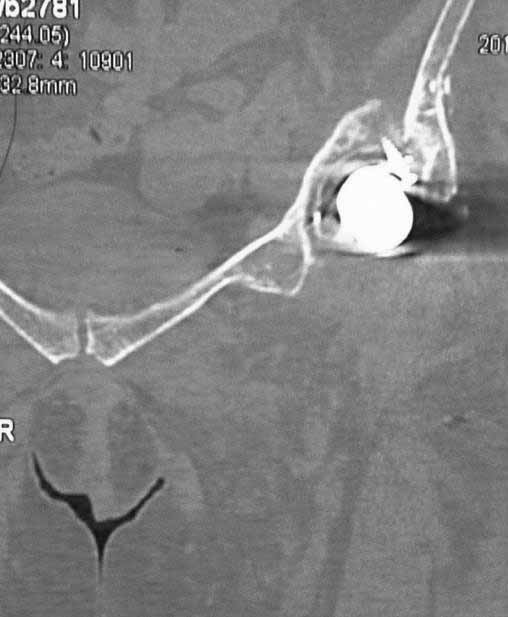

Пациентка 45 лет. Бесцементное эндопротезирование левого тазобедренного сустава 6 лет назад (впадина RM, Mathys, металл-металл, ножка Зульцеровская). За 10 лет до протезирования – коррегирующая остеотомия бедренной кости, которая не срослась в течение года до удаления пластины, а затем срослась в течение 3 месяцев иммобилизации в кокситной повязке. После протезирования получилось наблюдать пациентку почти постоянно, поскольку через 2 года синтезировал ей лодыжки на оперированной стороне, затем, через несколько месяцев удалил фиксаторы, а в 2009г. резецировал мениск на противоположной стороне. Боли все эти годы не беспокоили. Пациентка чуть выше среднего роста, вес тела нормальный. Физические нагрузки переносила хорошо. Работает на 7 этаже без лифта. Год назад экстирпация матки по поводу лейомиомы больших размеров. Несколько месяцев назад появились боли в области левого тазобедренного сустава. При рентгеновском и КТ исследованиях (июль с.г.) – нестабильность тазового компонента. От предложенной замены протеза пациентка на тот момент, слава богу, отказалась. Через какое то время боли в области левого тазобедренного сустава практически полностью прошли, а около 2 месяцев назад появилось ощущение патологической подвижности таза и боли в паху справа, которые через некоторое время уменьшились, а потом снова усилились после значительных физических нагрузок (много ходила по песку на пляже, носила тяжести). Ежедневно принимала диклофенак. На рентгенограммах – переломы правой лонной кости. Сейчас госпитализирована из-за болей в паху справа. Боли слева не беспокоят. На фоне снижения нагрузок в стационаре боли значимо уменьшились. Способна ходить без средств дополнительной опоры.

На представленных снимках тазобедренный сустав до и сразу после операции, затем 2 снимка 2009г., когда ничего не беспокоило, затем КТ 2-х месячной давности и вчерашние рентгенограммы обоих тазобедренных суставов.